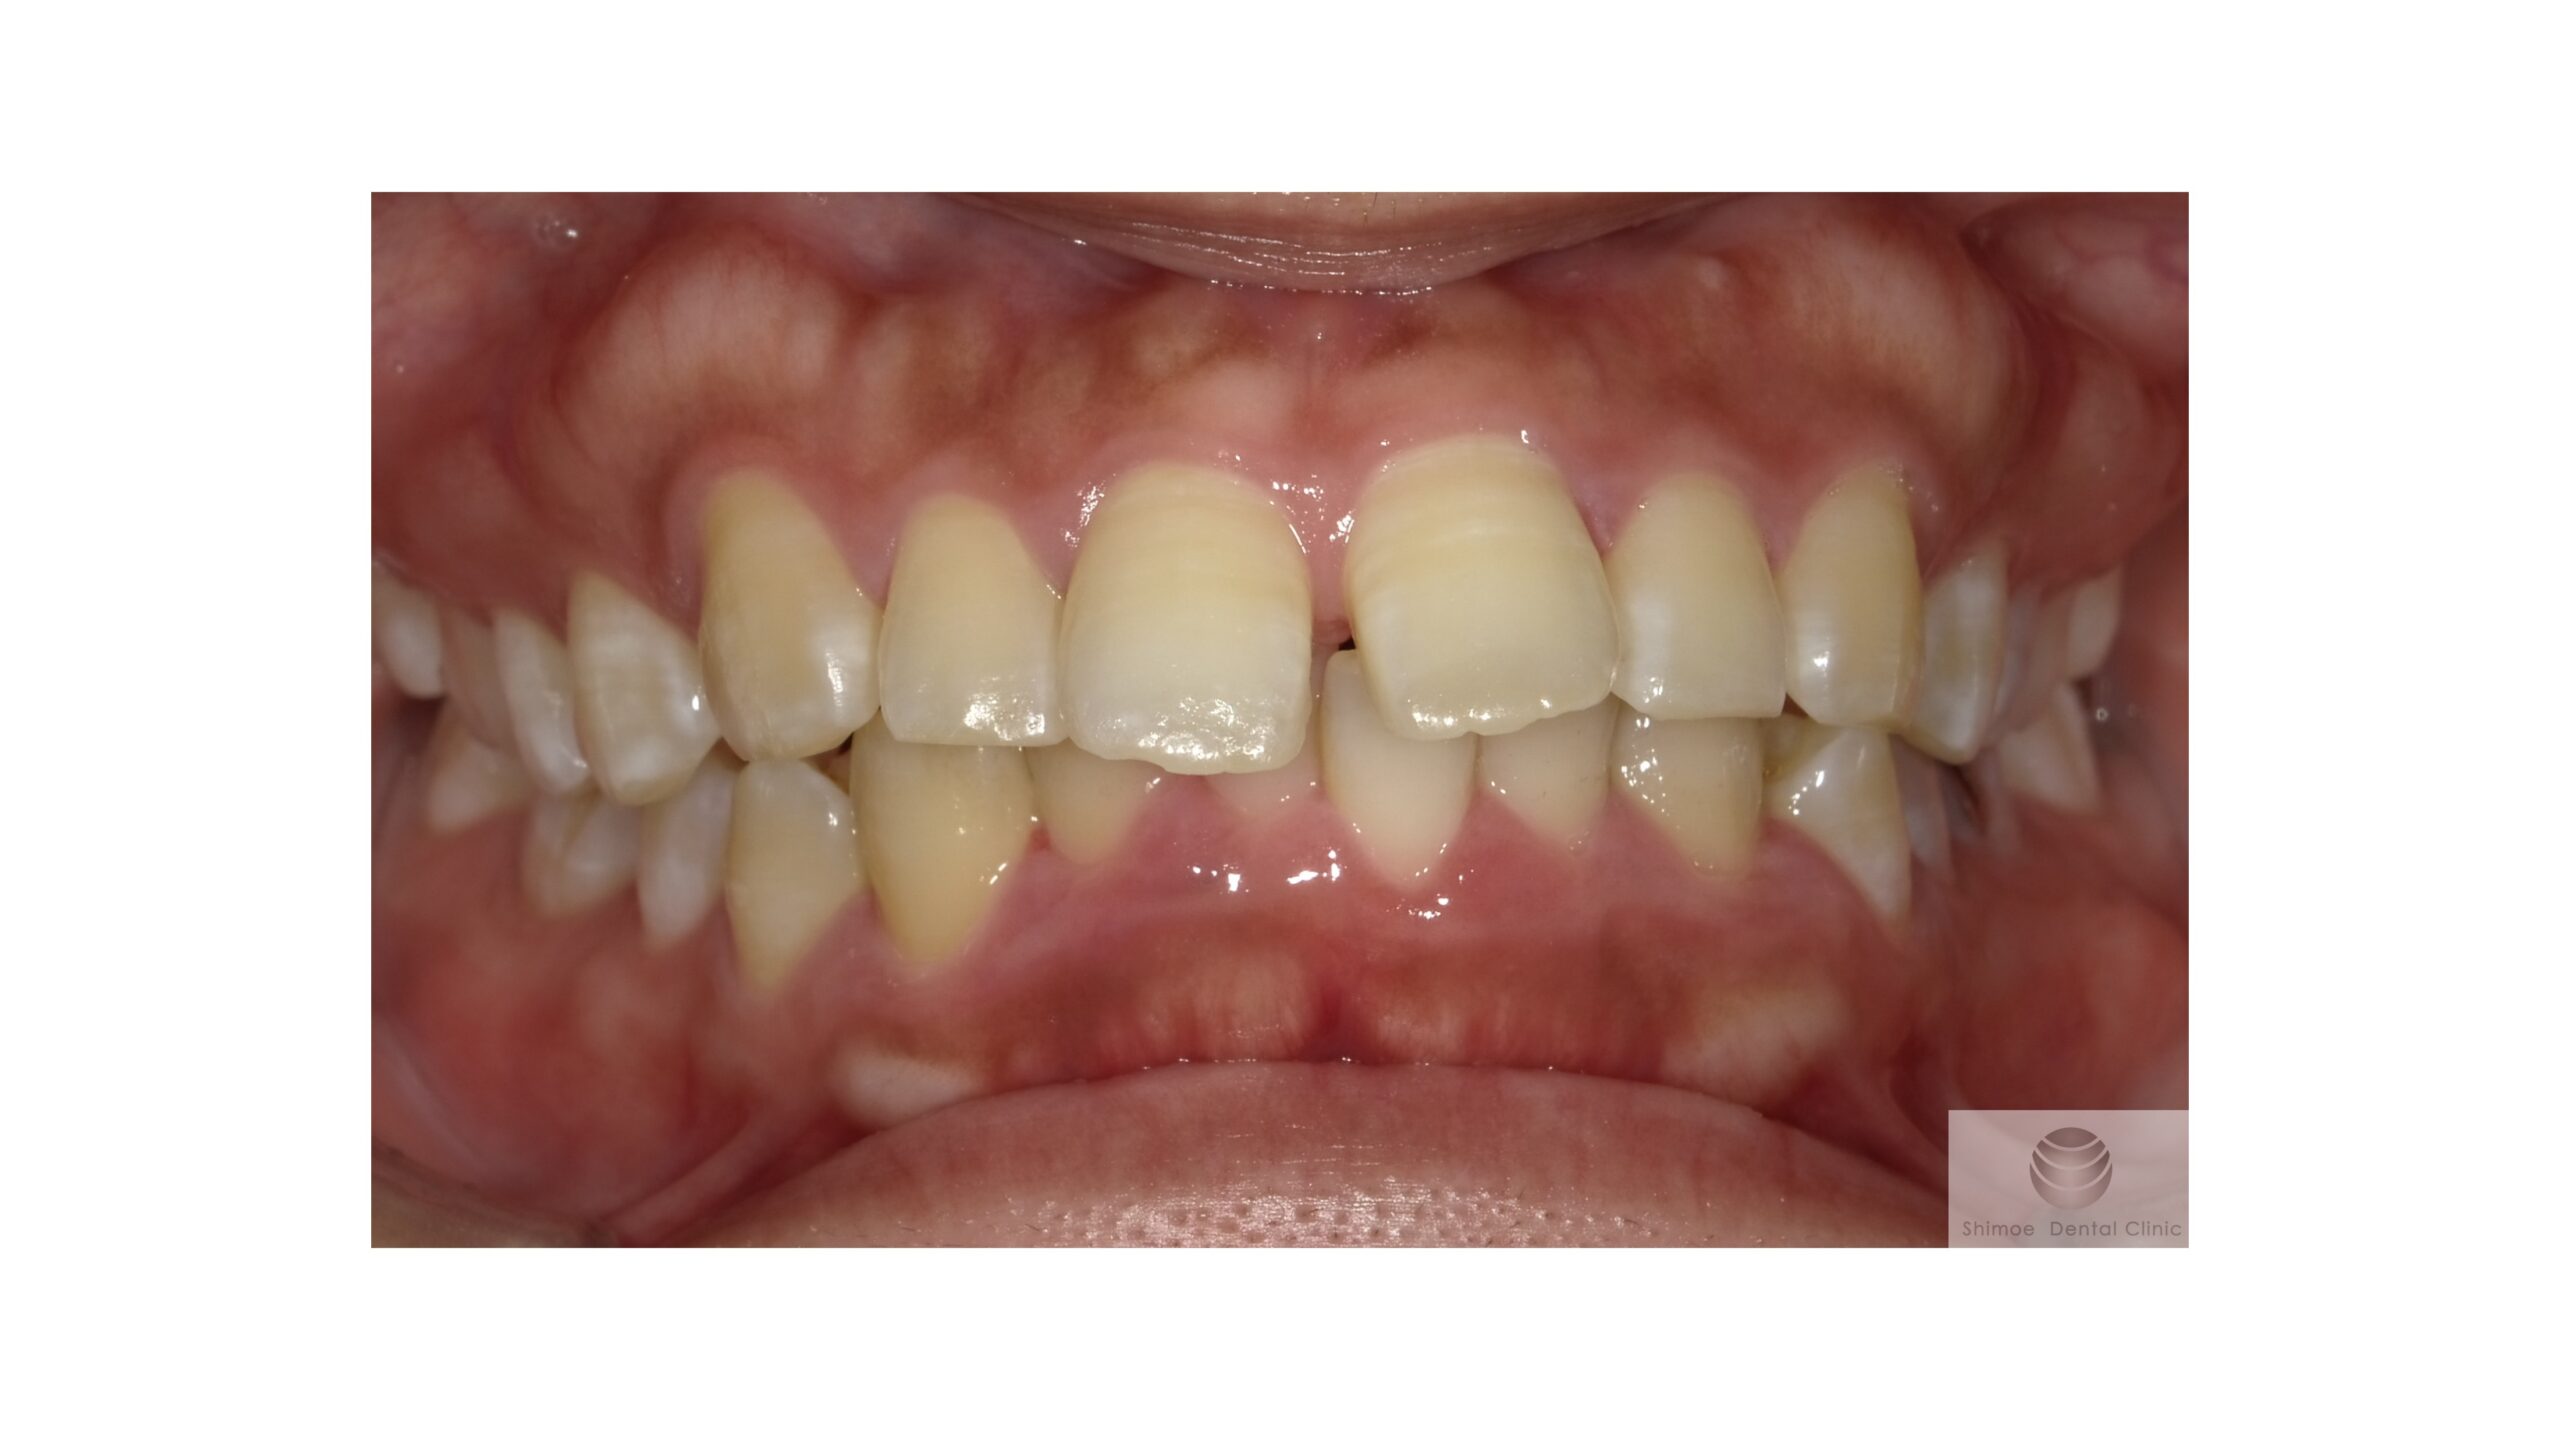

矯正後

矯正後 口腔内写真

骨隆起は上下の前歯部に大きくできています。

凸凹として審美的に気になられるとのことでした。

歯ブラシが当たったりすると痛むことがあります。